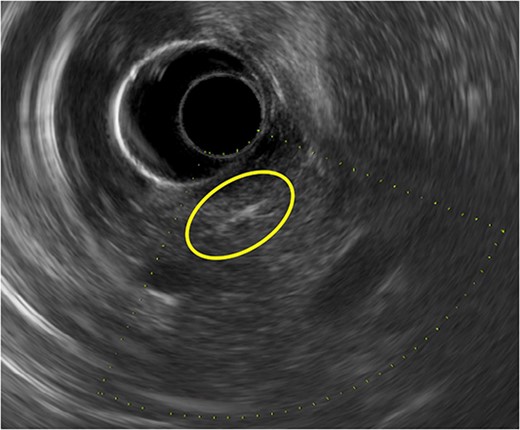

Gastroduodenoscopy showed normal mucosa of the duodenum without any foreign body. Endoscopic ultrasonography (EUS) detected a linear and straight highly echogenic substance in the parenchyma of the pancreatic head (Fig. 2). Using EUS, we predicted the foreign body to be a needle, not a fish bone.

A linear and straight highly echogenic substance is seen in the parenchyma of the pancreatic head on endoscopic ultrasonography.